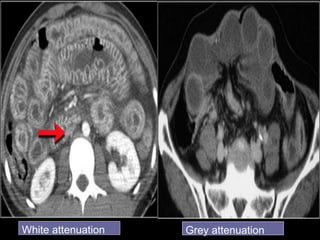

Paper thin bowel wall

White attenuation Grey attenuation

Water target sign Pneumatosis intestinalis

Water target signPneumatosis intestinalis

Signs of bowelgangrene:  Large amount of intraperitoneal fluid  Gas in the mesenteric / portal vessels  Intramural gas  Thinned bowel wall with poor or absent enhancement

• 49.